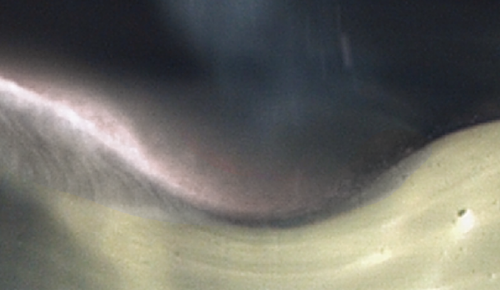

固体(アイス・ニードリング) VS 液体浸透比較

個体(アイス・ニードリング)

氷の粒子は衝突時に変形されずに表面を通り抜けます。これにより、薬剤を皮内へ浸透させることが可能です。

液体

液体は衝突時に変形されて表面から飛び跳ねます。よって、薬剤が液状で皮膚表面に残るようになります。

アイス・ニードリングは、表皮と真皮の境界にあたる表皮真皮接合部(DEJ)を正確にターゲットとしています。ターゲットクールを用いて希望の薬剤を導入することで、薬剤成分が表皮から真皮にかけて作用し、より効率的かつ素早い効果を実感いただけます。